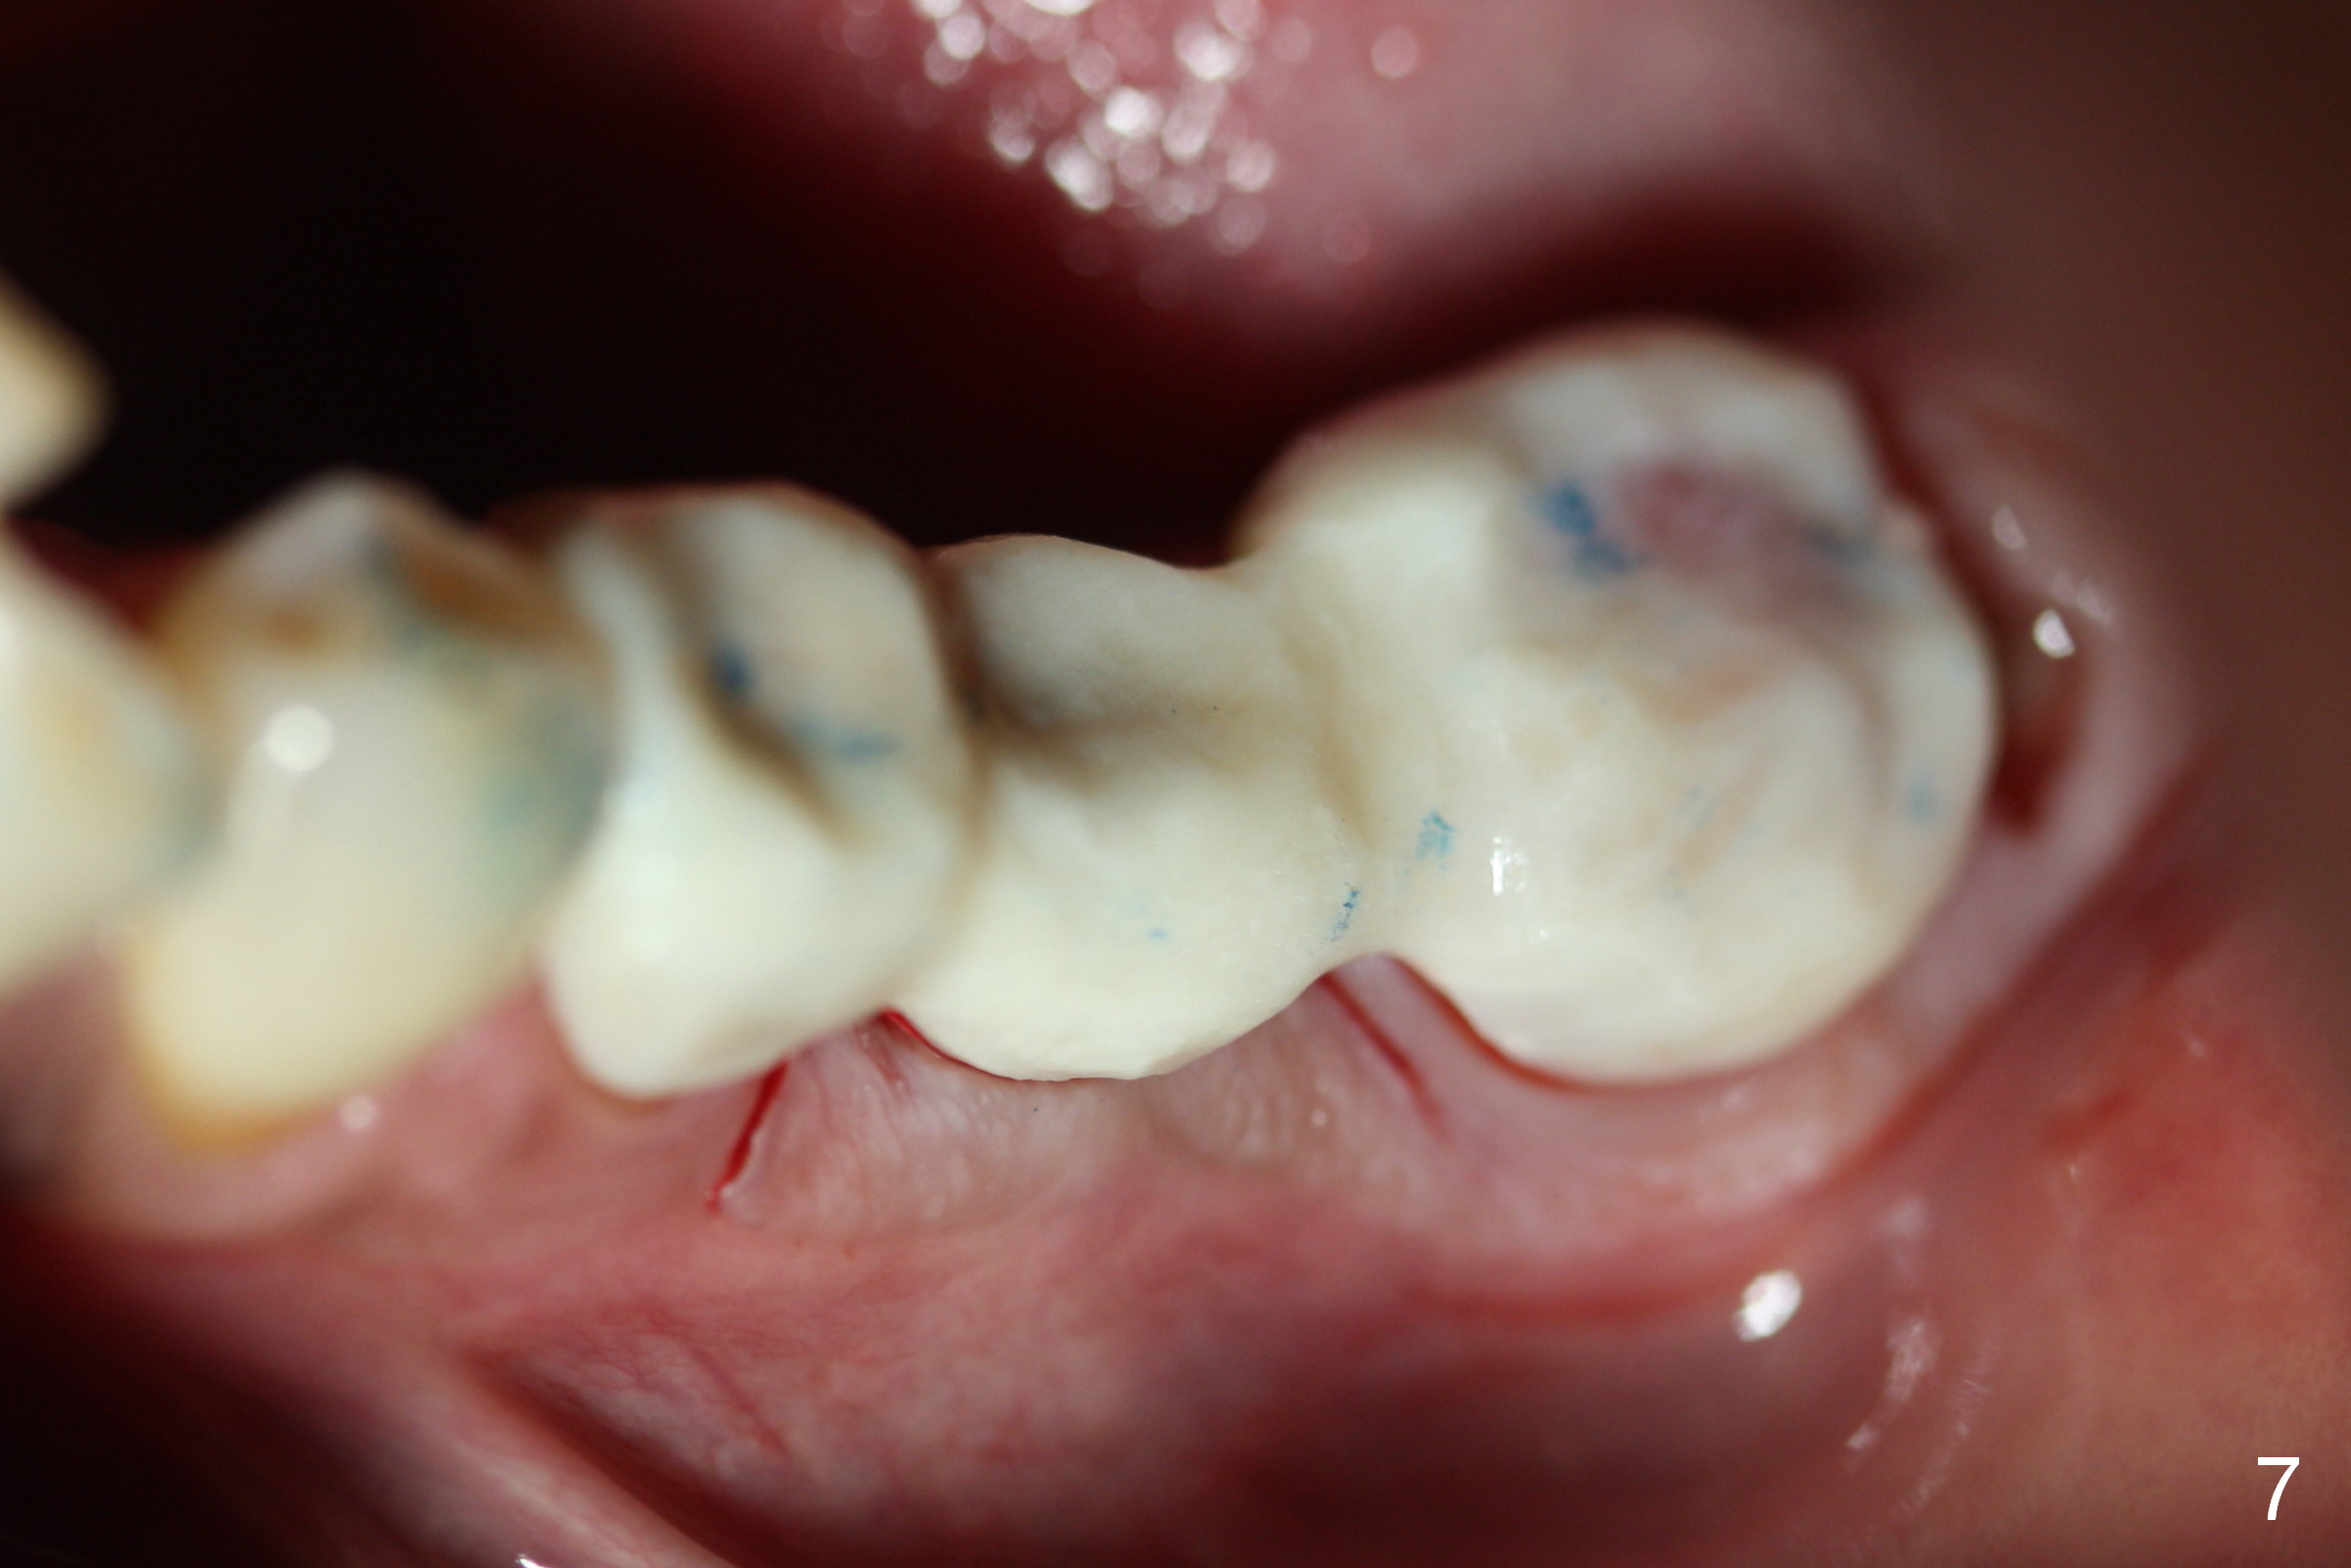

Since the implant is placed subcrestal mesially (Fig.4 >), the mesial margin of the abutment (5.8x4(3) mm) is subgingival (Fig.5 ^). An immediate provisional has to be made to keep the gingiva from growing into the margin. After occlusal clearance (Fig.6), the immediate provisional is seated (Fig.7). There is no paresthesia postop.